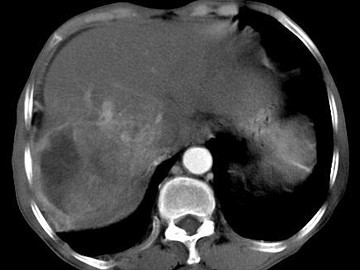

女,40岁,有口服避孕药史,肝区疼痛、腹部包块,AFP阴性,CT扫描如图,最可能的诊断是()

• A.肝细胞腺瘤

• B.肝再生结节

• C.结节性肝癌

• D.肝右叶巨块型肝癌

• E.肝黄色肉芽肿